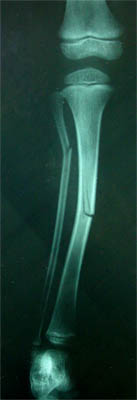

1.

Which type of bone is seen in the following image?

This child was playing soccer and missed the ball, kicking a bleacher instead. What type of fracture did she experience? (it is the same for each bone shown)